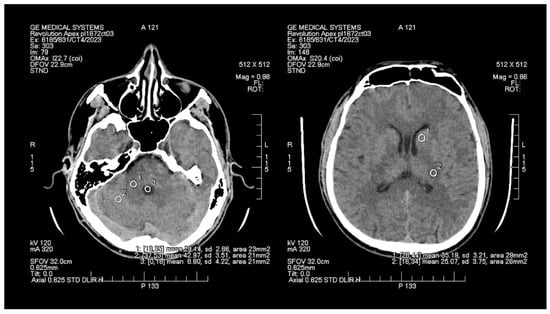

The objective assessment of image quality involved analyzing the signal-to-noise (SNR) and contrast-to-noise (CNR) ratios. To maintain consistency, a control variable was introduced in the form of manually set Regions of Interest (ROIs), which are analogous and predefined study areas in each pair of images. The average size of the ROI area was 24 mm2, with the smallest and the largest areas measuring 20 mm2 and 29 mm2, respectively. ROIs were positioned manually on the ASIR-V (Figure 1) reconstruction image, and then, duplicated at identical coordinates on the DLIR (Figure 2) reconstruction, which excluded potential deviations resulting from the lack of homogeneity of the measured tissues. The designation of the slice subject to the assessment was based solely on the anatomical factors of the patient. The first two ROIs were located in the white matter of the posterior limb of the internal capsule and the grey matter of the caudate nucleus, while the other two ROIs were positioned in the white and grey matter of the cerebellum. The fifth ROI was set in the cerebrospinal fluid of the fourth ventricle. To determine the signal level and noise, the mean CT number (mean) within the ROI and the standard deviation (SD) were taken into account.

Figure 1. Images of head CT with marked ROIs located in BGA (basal ganglia area) and PCF (posterior cranial fossa) obtained using FBP + ASIR.